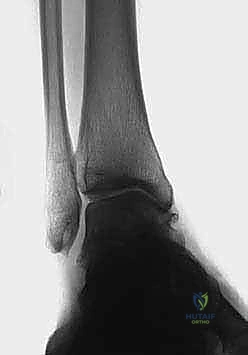

2. التصوير بالأشعة السينية بوضعية الوقوف (Weight-bearing X-rays)

هذا هو حجر الأساس في التشخيص. الأشعة العادية والمريض مستلقٍ لا تظهر الحجم الحقيقي للتشوه. يطلب الدكتور هطيف صوراً خاصة والمريض يحمل وزنه كاملاً على قدميه.

* المنظر الأمامي الخلفي (AP View): لتقييم المسافة المفصلية وتحديد زاوية سطح الساق (Tibial Anterior Surface Angle - TAS).